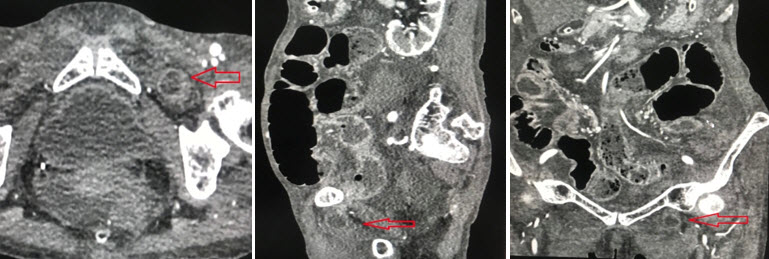

Chụp cắt lớp vi tính ổ bụng: các quai ruột non giãn kèm mức hơi dịch (h/a tắc ruột ). Hình ảnh quai ruột non chui qua lổ bịt trái. Dịch tư do ổ bụng lượng vừa. Tràn dịch màng phổi 2 bên lượng ít. (Hình 3).

thoatvi3

Hình 3. Hình ảnh CT scan của thoát vị đùi- Mũi tên đỏ là quai ruột thoát vị